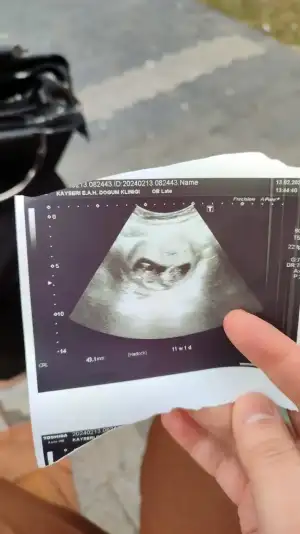

Arkadaşlar lütfen anlayanlar bakabilir mi

16 haftada nasıl belli olmaz ki çok şaşırdım , kız sanırım bacak arası kapalı olıyor kız bebeklerin genelde o yüzden göremedi16 haftalık hamileyim doktor cinsiyeti belli değil dedi ama çok merak ediyorum bilen varsa yazabilir mi

Gerçi kız gibi de. 2. Fotoya bakacaksınız o çıkıntının sırt ile olan açısına bakılıyırSanki oğlan gibi, nub theory diye bişi var inceleyin anlarsınız.

Kız bence cnm öğrendin mi cinsiyetini16 haftalık hamileyim doktor cinsiyeti belli değil dedi ama çok merak ediyorum bilen varsa yazabilir mi

Hayır öğrenemedim maalesef yurt dışındayım geç söylüyorlar burda 13 haftalıkken gittim erkeğe benziyor ama emin değilim dediKız bence cnm öğrendin mi cinsiyetini

16 haftada nasıl belli olmaz ki çok şaşırdım , kız sanırım bacak arası kapalı olıyor kız bebeklerin genelde o yüzden göremedi

Birde bunlara bakar mısın canım yurt dişnda geç söylüyorlar henüz öğrenmedim meraktan patlicam vallaGerçi kız gibi de. 2. Fotoya bakacaksınız o çıkıntının sırt ile olan açısına bakılıyır

Ya hiç göstermemiş ki nub kısmını. Erkek gibi geldi ama emin olamadım.Birde bunlara bakar mısın canım yurt dişnda geç söylüyorlar henüz öğrenmedim meraktan patlicam valla

Siz söyledikçe dikkat ediyorum gerçekten öyle mi acaba

Bence bariz öyle yaaaSiz söyledikçe dikkat ediyorum gerçekten öyle mi acaba

Canım alın kısmı düzse erkek bombeliyse kız diye biliyorum erkeğe benziyo benceSiz söyledikçe dikkat ediyorum gerçekten öyle mi acaba

Bana da yanında bulunabilir mısınız 11+1